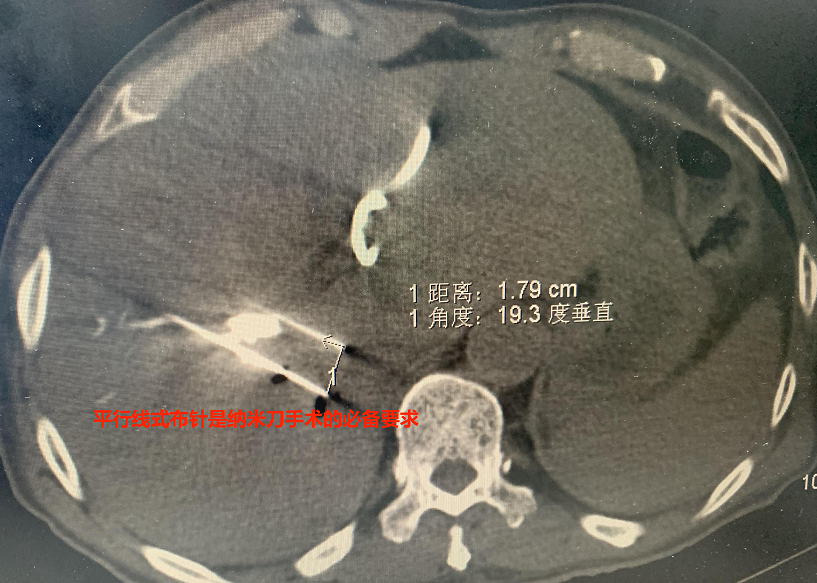

術(shù)中即刻影像資料